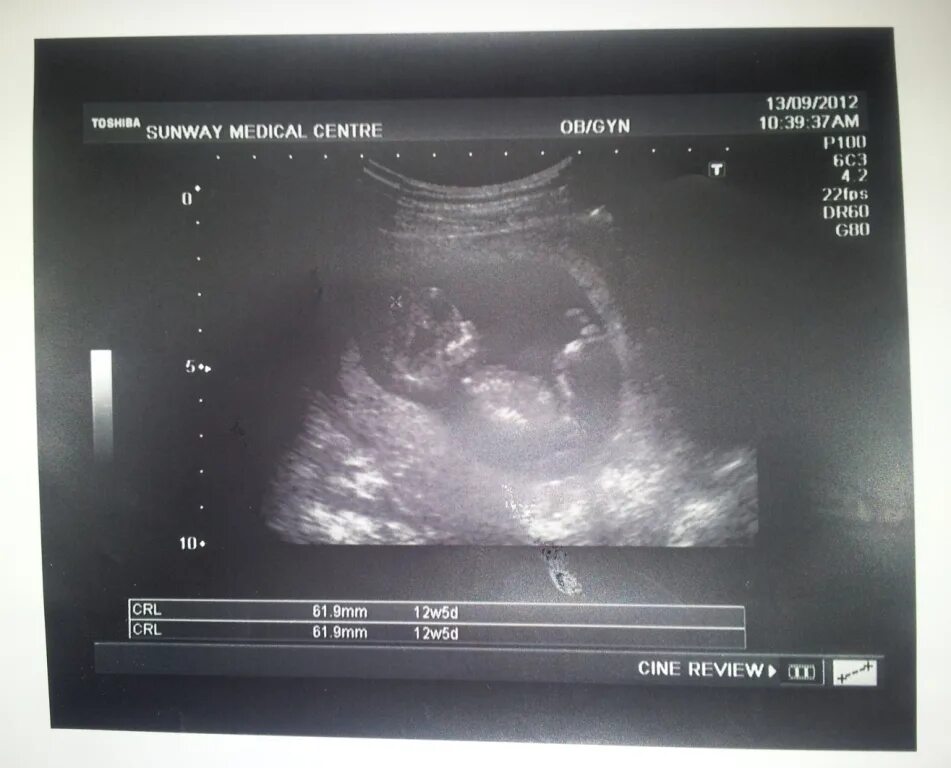

Тянет живот на 12 неделе